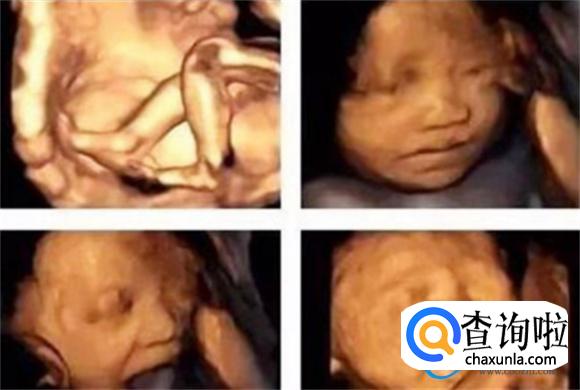

四维彩超技术在现代医学中应用广泛,尤其在孕期检查中,可以帮助孕妈妈们更全面地了解未出生的胎宝宝的生长发育状态和活动变化。通过四维彩超,可以观察到胎宝宝的实时动态画面,包括身体躯干、器官活动以及性别等信息。四维技术的到来,可以使得我们可以多维度、多角度、多方位地了解、观察到母体中胎宝宝的生长发育状态和活动变化的。同时,也有助于早期发现一些胎宝宝的先天性疾病,提供了很有力的科学依据。

对于很多孕妈妈们来说,想要早点知道胎宝宝的长相、面部、身体的轮廓、结构如何,这都是很正常的事情。而四维超声技术可以帮助孕妈妈们实现这个愿望。孕期时的四维打印的胎宝宝的照片和出生后的宝宝的长相和各种体态基本上是相一致的。由于四维超声技术的稳定性,宝宝的五官位置还有各个具体的躯干样子都是在四维彩超下看的一清二楚的。因此,孕妈妈们不必过于担心。